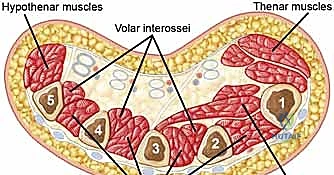

The hand comprises ten distinct, tightly enclosed fascial compartments. These include four dorsal interosseous compartments, three volar interosseous compartments, the thenar compartment, the hypothenar compartment, and the adductor pollicis compartment.

Decompression of the hand requires releasing the interosseous, thenar, and hypothenar compartments. Two longitudinal dorsal incisions are typically utilized: one centered over the second metacarpal (to access the first and second dorsal interossei) and one over the fourth metacarpal (to access the third and fourth dorsal interossei).

Blunt dissection is carried down alongside the metacarpal shafts to decompress the volar interossei and the adductor pollicis. The thenar and hypothenar compartments can be decompressed via separate small longitudinal incisions on the radial and ulnar borders of the hand, respectively.